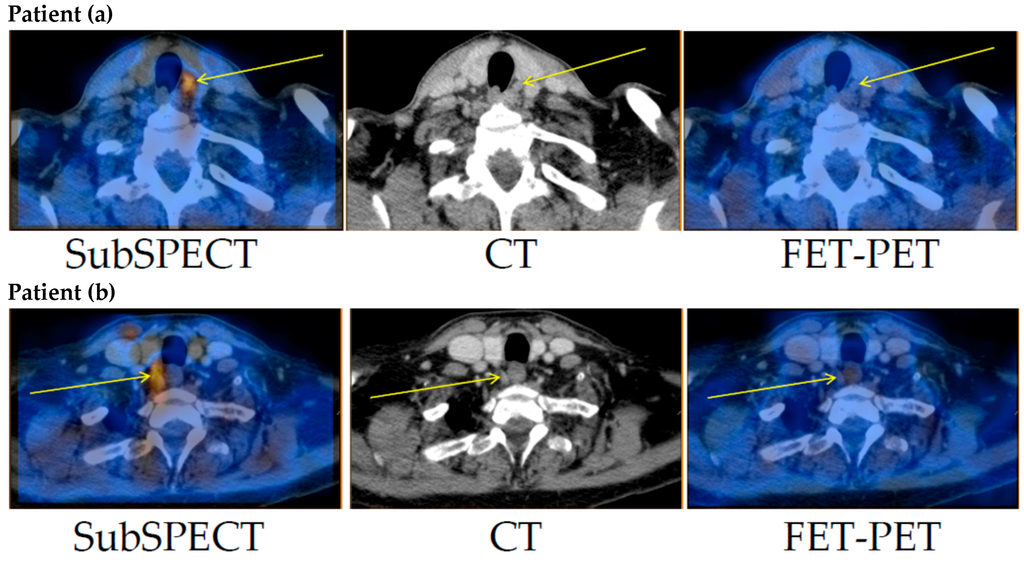

Only faint FET uptake was detected in both thyroid tissue and the parathyroid adenomas (Figure 1). Excluding an obvious vascular phase during the first 10 min, TBRmax (for definition please refer to Materials and Methods) was reached between 30 and 35 min post-injection. TBRmax in patients (a) and (b) was 1.5 and 1.7, respectively. Thus, no clinically relevant differential uptake of FET could be detected in the parathyroid adenomas in either of the two patients (Figure 2).

Figure 1. Tracer-uptake in the parathyroid adenomas in patients (a) and (b). Left: Subtraction (Tc-99m-sestamibi minus I-123)-SPECT/CT. Middle: CT. Right: FET-PET/CT. Thin arrows mark the surgically confirmed location of the parathyroid adenoma. FET: O-2-(18F)fluoroethyl-l-tyrosine; PET: positron emission tomography; SPECT/CT: single photon emission computed tomography/CT.